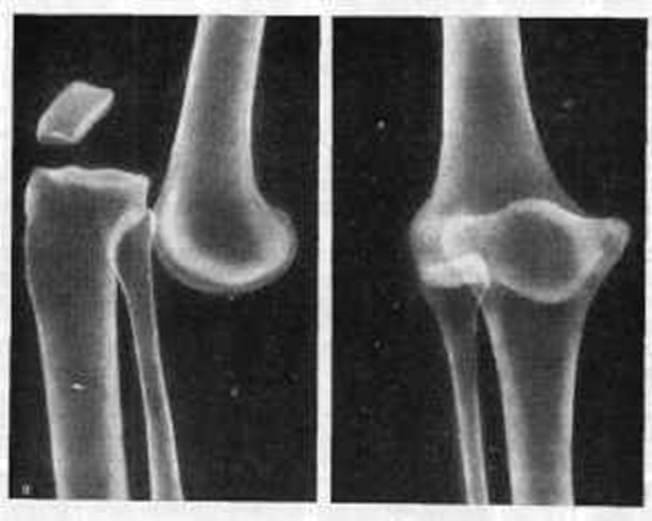

- Вывих чашечки, при котором происходит повреждение патело-феморального сочленения, соединяющего бедренную кость и надколенник. Встречается подобная патология не так и часто, и обычно связана с прямым ударом по коленке, резким сокращением бедренных мышц во время отрывистого движения. В группу риска для такого повреждения попадают, прежде всего, спортсмены. Встречается и диспластический, то есть врожденный вывих надколенника, чаще у девочек. Однако последствий можно не опасаться, если вовремя начать лечение.

- Вывих голени, который и принято в немедицинской среде именовать вывихом колена. При такой травме расходятся большеберцовая кость и бедренная, то есть повреждается сустав, расположенный между костями. Нередко такое повреждение сопровождает разрыв или надрыв мениска коленного сустава, связок. Это сочленение хорошо защищено от внешних воздействий. Поэтому для получения подобной травмы нужно довольно сильное воздействие, связанное с ротацией или движением голени, в то время как бедро остается зафиксированным. Такие повреждения происходят во время автодорожных происшествий, при падениях со значительной высоты.

Боковые смещения проявляются в виде отклонений голени в сторону, заднее и переднее выглядит как ступенька, образованная большеберцовой костью.

Именно такой вывих подразумевается чаще всего при постановке диагноза. Встречается смещение коленной чашечки в сторону, также она может проворачиваться, то есть речь будет идти о торсионном смещении.

Чаще встречается смещение, имеющее боковое отклонение. Причина такой патологии связана с осложнениями гонартроза, деформации ног в колене. При этом пациент не жалуется на сильные боли, а во время движения ощущается провал в суставе.